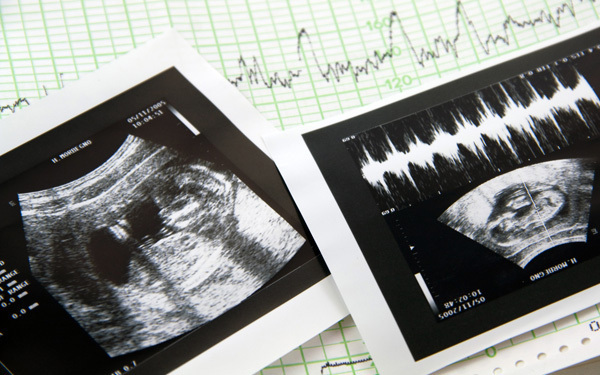

妊娠4ヶ月のエコー(超音波)写真

© wlablack - Fotolia.com

胎盤がほぼ完成し、機能し始めます。赤ちゃんも骨や筋肉が発達し、体の動きが活発に。ますます人間らしい動きを見せてくれます。

妊娠12週のエコー写真

骨や筋肉が発達し、羊水の中で動き回る

骨の成長がさらに進み、頭蓋骨もはっきり見え始めます。羊水の中を元気に動き回る赤ちゃんの様子が見えるでしょう。骨の発達で首と頭がまっすぐになるので、そのシルエットから染色体異常や先天性の疾患などを慎重に観察します。運が良ければ羊水を飲んだり吐いたりする、呼吸のような動きが見られる場合も。